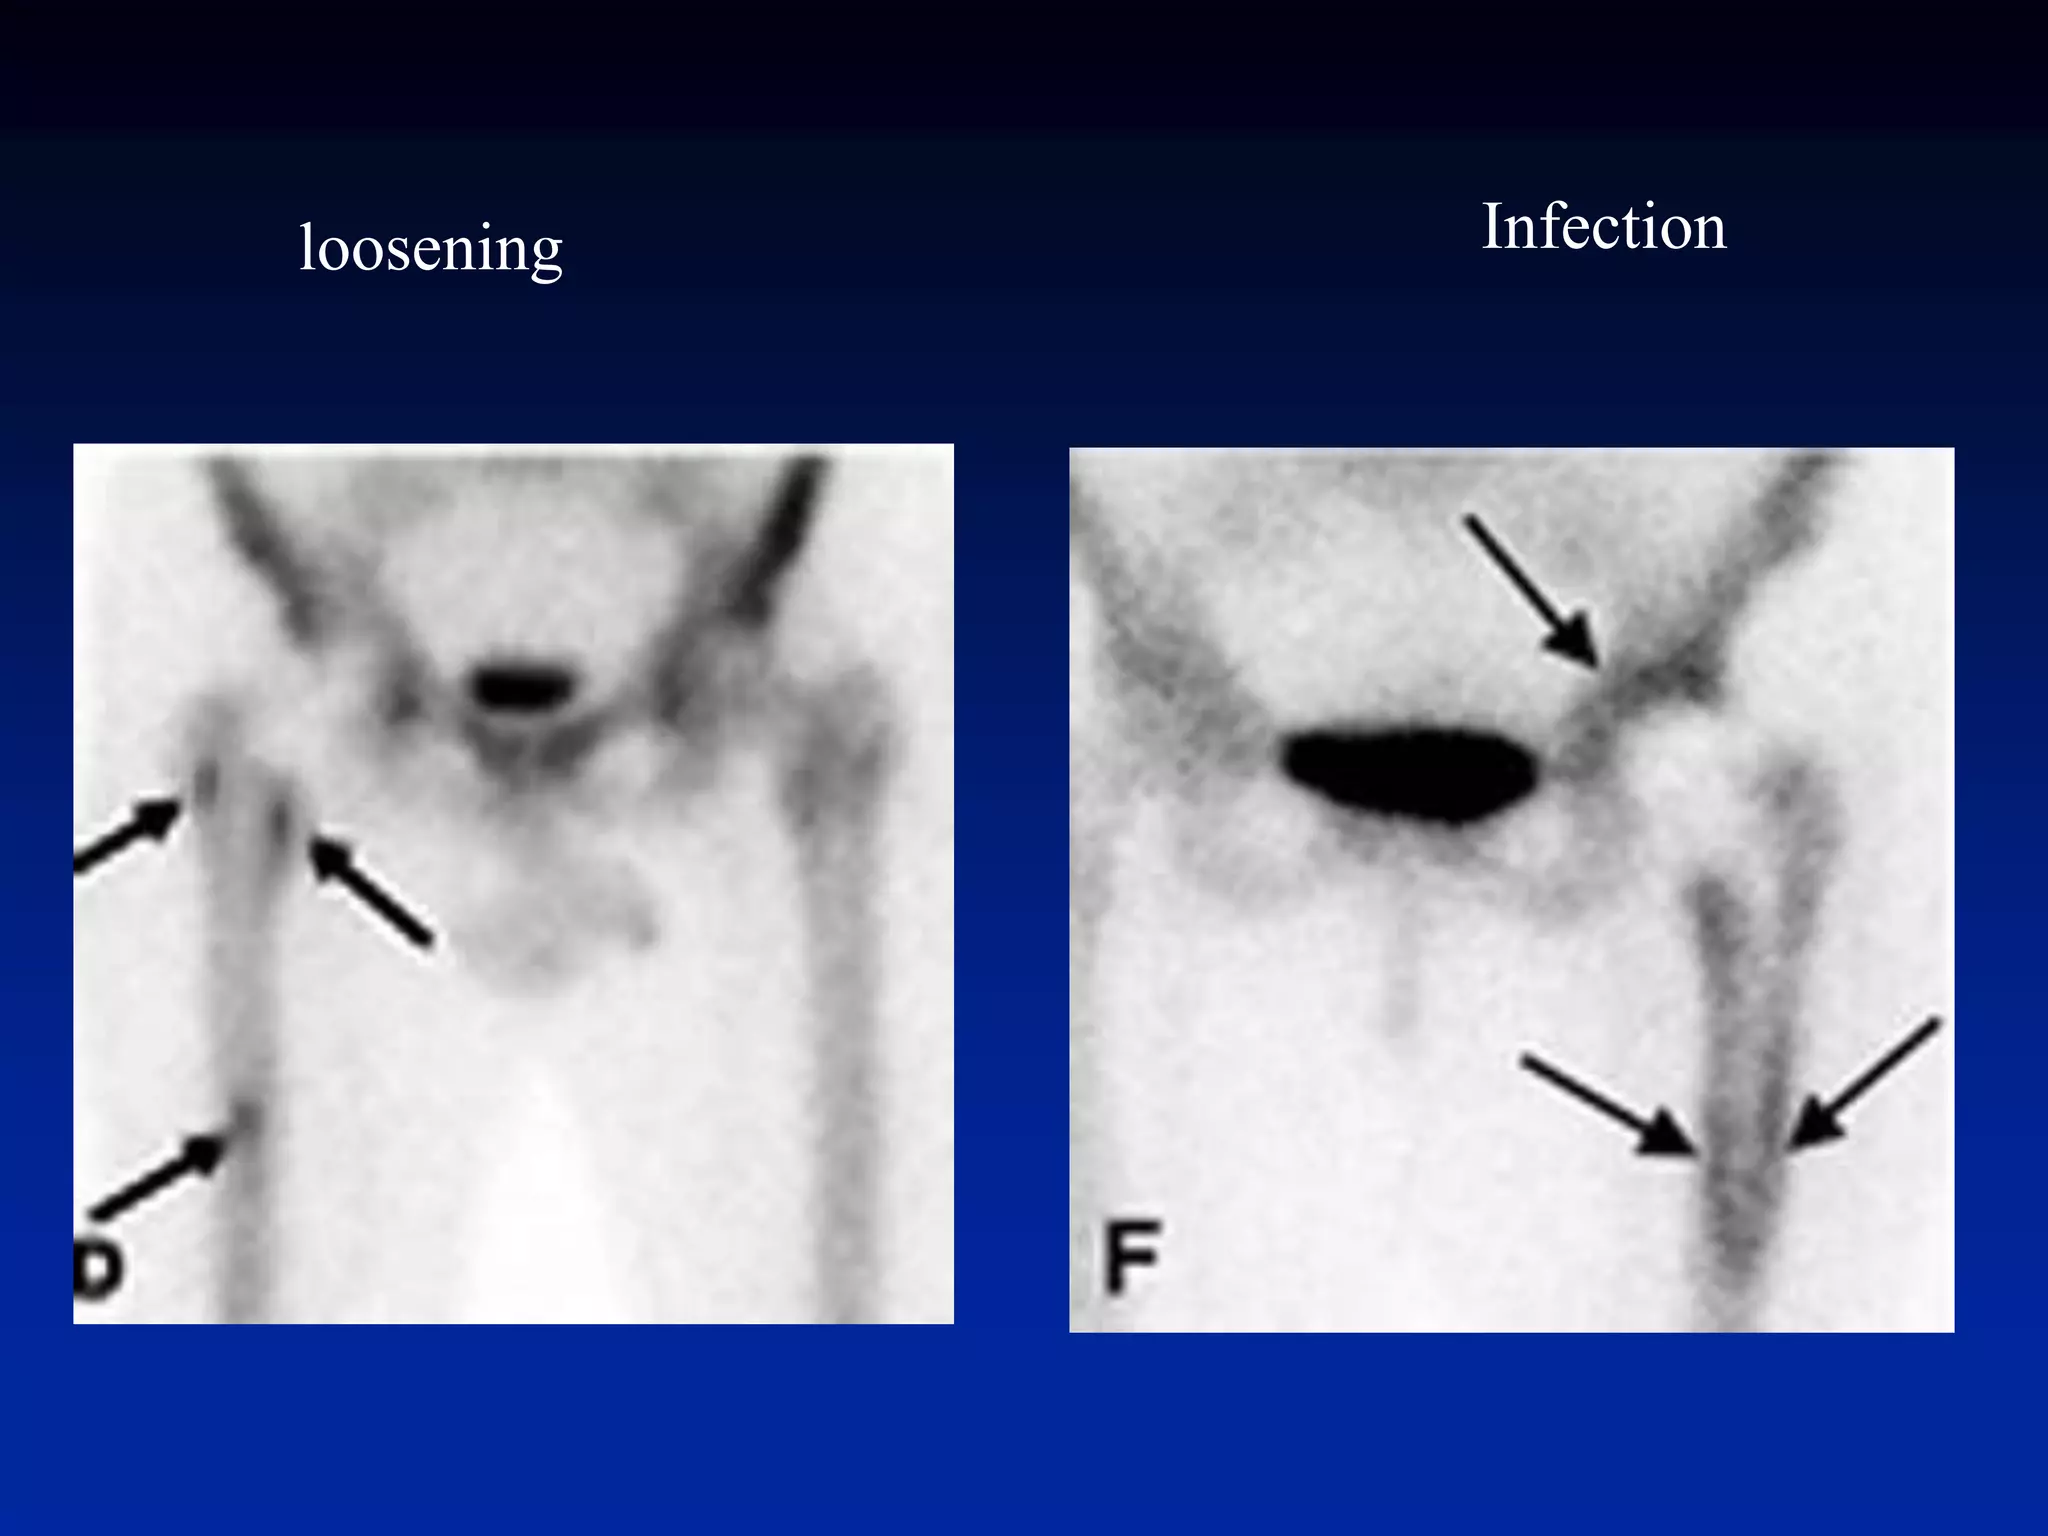

Prosthesis-Loosening vs

Infection

Infection from loosening

l

loosening Infection

Prosthesis-Loosening vs Infection • increaseduptake normal after surgery –~1y w/ cemented, ~2-3y w/ non-cemented • start w/ bone scan if negative no infection or loosening • if positive and unclear whether loosening or infection consider Tc- HMPAO-WBC scan to differentiate Infection from loosening l